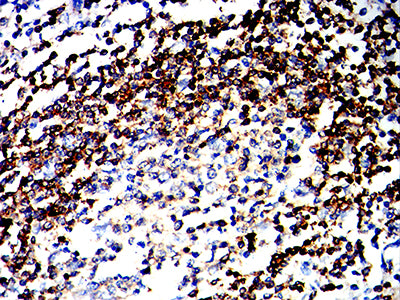

TD-323183.jpg

Immunohistochemical analysis of paraffin-embedded human Esophageal cancer tissues using CD180 mouse mAb with DAB staining.